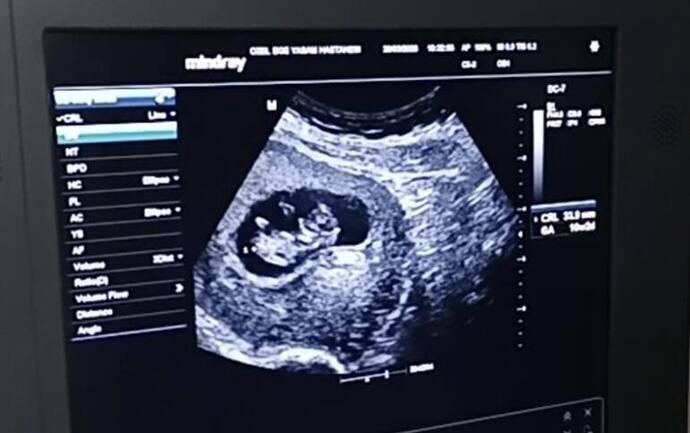

Hep ben tahmin yapıyordum kızlar şimdi ben sizden tahmin bekliyorum Bizim cinsiyetimiz ne teyzeler yorumlarınızı bekliyorum…

Allah nasip ederse inşallah 4. gebeliğim canım